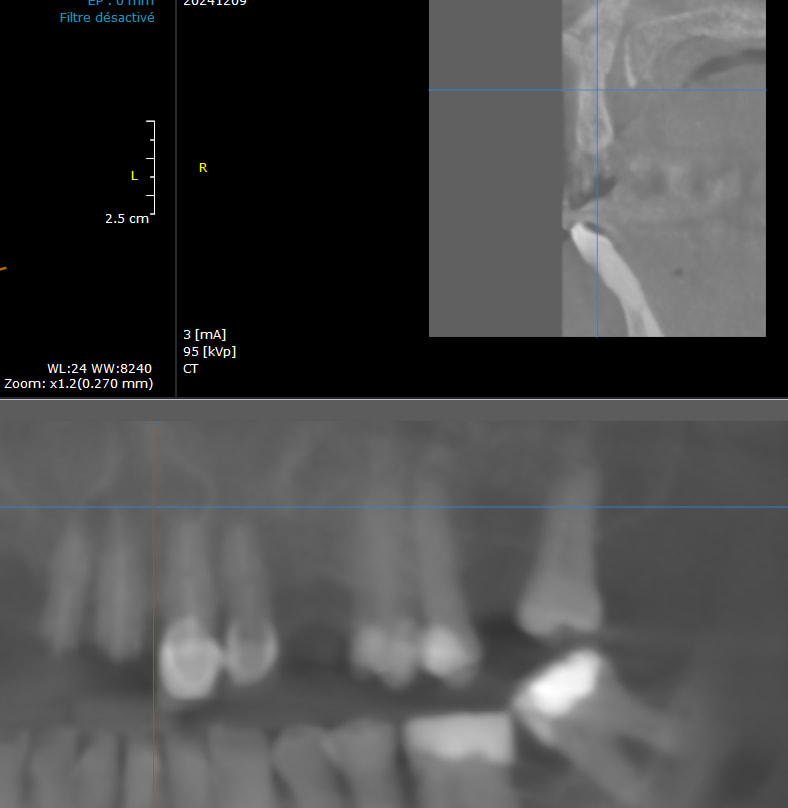

J'aimerais bien avoir vos avis, car j'ai jamais vu un canal palatin aussi gros et je soupçonne un kyste associé (alors qu'aucune des dents antérieure ne bouge, et aucune fistule/suppuration....et c'est là que je me pose des questions....)

donc en gros avez vous déjà vu des cas comme çà?

Il faut choisir des coupes obliques parallèles aux canaux traités, c’est probablement endo.

Il faudrait également une coupe transversale.

Étant endodontiste, cela ne ressemble pas du tout à un kyste endodontique mais je pencherai plus pour un kyste embryologique type naso palatin provenant du canal du même nom et de ses restes embryo.

Mais d’autres coupes sont nécessaires

Pas de rapport avec l'apex du canal traité et pas de signe d'autre canal.

Le kyste naso palatin est plausible, surtout si aucun symptôme.

En regardant sur le livre oral radiology de Stuart C. White ca ressemble beaucoup à un kyste naso palatin d'origine embryonnaire.